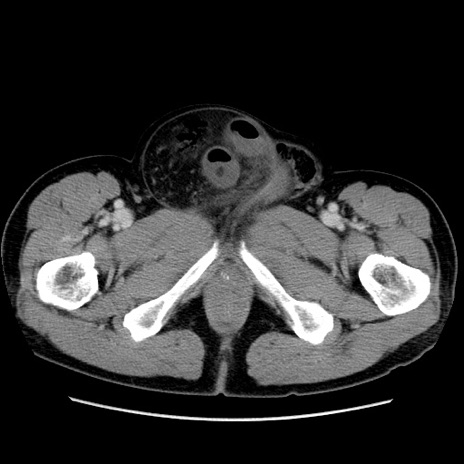

症例34(横断像)

【症例】60歳代 男性

【主訴】右鼠径部膨隆

【現病歴】1年程前より右鼠径部膨隆あり。自己にて還納可能だったため放置していた。3時間前より右鼠径部の脱出を認め、還納困難となり受診。

【既往歴】高血圧

【身体所見】右鼠径部に小児頭大の膨隆あり。弾性硬であり、用手還納は困難。左鼠径部にも膨隆を認める。脱出はなし。